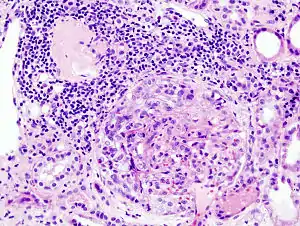

| Histopathological image of crescentic glomerulonephritis in a person with MPO-ANCA positive rapid progressive glomerulonephritis. Hematoxylin & eosin stain. | |